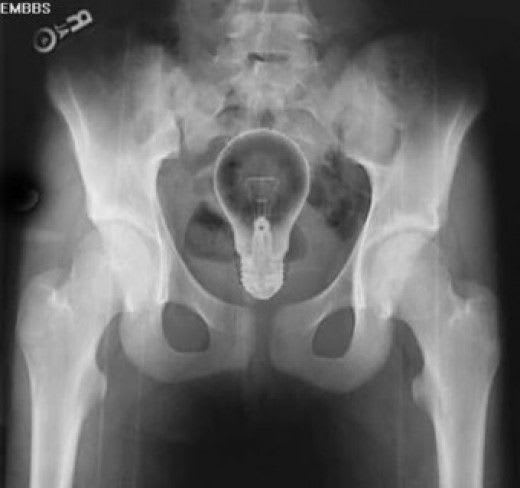

Dr. Kelso: So what do you think, Perry?

Dr. Cox: Well I tell you there, Bob-o, either this kid has a light bulb up his butt or his colon just had a good idea.